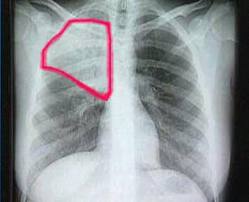

Los síntomas que pueden mostrar son fiebre, anorexia, depresión, y dificultad para respirar, abdomen distendido, diarrea y cianosis. En la fase final sangran por la nariz, y pueden presentar convulsiones, entrando en coma y muriendo por deficiencia de coagulación que produce hemorragias internas en diversos órganos.